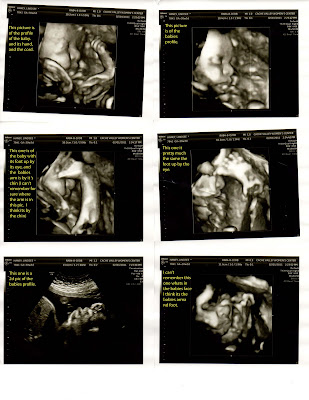

When I went in for my 28 week apt. (I think it was 28 weeks) I was measuring a week in half big. so to be on the safe side my Dr . wanted me to get an ultrasound to see if the baby was big or if I could have extra fluid. Everything came back fine with the ultra sound. It was so fun to see the baby again. It was really nice to be able to have Dan there for that apt. He was able to finish work early and able to go the the ultra sound. I hope I remembered everything right on the ultrasound pictures.

(if you click on the picture it should make them bigger)